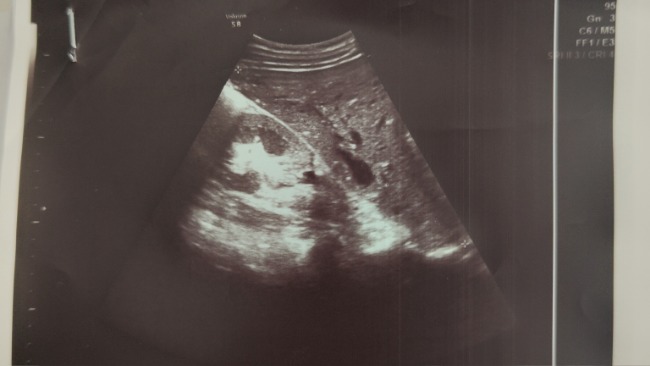

Badania wykazały obecność dużego guza oraz zmian w wątrobie i śledzionie. Lekarze nie pozostawiają złudzeń – choroba jest bardzo poważna i wymaga natychmiastowego, intensywnego leczenia onkologicznego. Angelika zamiast cieszyć się młodością, musi każdego dnia mierzyć się z bólem, strachem i niepewnością o jutro.